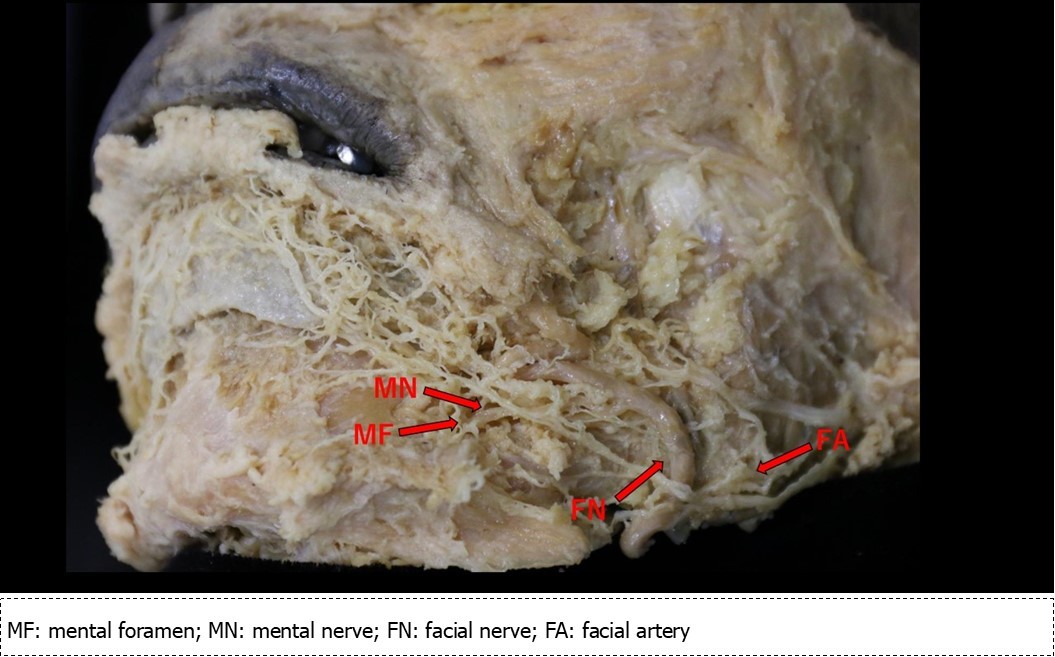

Five samples (age range: 72 to 86) were obtained from the Department of Anatomy at Tokyo Dental College, and their use in research required approval by the university ethics committee (Yamamoto M, No. 922). The samples consisted of five Japanese adult male cadavers fixed in 10% formalin. Surface dissection was performed using the standard methods. The skin of the face was dissected using scalpel, tweezers, and shears. Next, the fatty tissue, connective tissue, dermal muscles, and associated tissues were removed to allow the vasculature and nerves to maintain their original positions. We were careful to ensure that the natural placements of these structures were preserved despite the loss of supportive tissue. First, we confirmed the location of the mental foramen. Then, as the communicating branch of the mental nerve and facial nerve were identified at the chin and lower lip, we dissected the facial nerve to the anterior margin of the parotid gland to observe the marginal mandibular branch (Figure 1). Next, we removed the wall formed by bone on the buccal side of the mandibular canal to enable observation of the nerves and blood vessels within the buccal canal. Bone removal was performed using a saw and mallet to break up the cortical bone. Using tweezers, we grasped bone fragments and removed them. The inferior alveolar nerve was removed from the mandibular canal to preserve the connectivity between the mental and facial nerves.

Figure 1.Dissection of the region of the mental nerve and the marginal mandibular branch of the facial nerve

The mental nerve (Figure 2) emerges from the mental foramen and advances 5 mm in a posterosuperior direction, at which point the anguli oris branch branches in a superior direction. It then curves in an anterior direction and, at approximately 3 mm, it branches into three. The inferior labial branch moves in an anterosuperior direction to innervate the lower lip. Moving in a distal direction, the first and second of three branches form from the same trunk. On the external side of this common trunk, a branch off the inferior labial branch advances 2 mm, at which point the mental nerve forms a common origin with the inferior labial branch. This mental nerve then turns toward the anteroinferior direction and enters the mentalis muscle.

Figure 2.Sketch of the mental nerve, marginal mandibular branch of the facial nerve and the facial artery

The various branches of the mental nerve belong to a communicating branch that joins with the marginal mandibular branch of the facial muscle. In addition, a relatively thick branch of the marginal mandibular branch of facial muscle communicates with the inferior arterial arch of the alveolar artery and the facial artery at the mental foramen. This characteristic was similar among all specimens.

Marginal Mandibular Branch of the Facial Artery

Two branches extend from the anterior margin of the inferior corner of the parotid gland. The superior branch runs parallel to the mandibular base, while the inferior branch runs anteriorly along the corner of the mandible, after which (and immediately before encountering the facial artery and vein) it branches off into two branches. The first branch follows the inferior margin of the mandible, and the second branch turns in an anterosuperior direction. The latter of these two passes across the facial artery, vein, and mentalis branch of the facial artery and reaches the lower lip. During its course, at the point immediately after passing over the mentalis branch, it fuses with a the buccal branch of the facial nerve, and the branches that arise from this fusion advance toward the lower lip (2 branches) and mentalis (1 branch), enter the mental foramen (1 branch), and a fine branch (1 branch) runs in a posterior direction toward the facial artery. The branch that moves toward the lower lip is a branch that communicates with the anguli oris branch and inferior labial branch (Figure 2, C1-7). The branch that advances toward the mentalis adheres to the mentalis branch of the mental nerve (Figure 2, C8), and the branch that enters the mental foramen adheres to the inferior alveolar nerve immediately after entering the mandibular canal (Figure 3F). There is one fine branch that branches off from the fusion point and advances toward the facial artery (Figure 2※). Prior to the fusion point, there was a branch that branched off the buccal branch and advanced toward the facial artery. The left inferior labial artery was missing, but a similar feature was observed in all specimens.

Communication between the anguli oris branch and marginal mandibular branch occurred at a point 1.5 cm from the anguli oris and advanced in a posteroinferior direction at a 45-degree angle (Figure 2, C1)

Communication between the inferior labial branch and marginal mandibular branch at the center of the lower lip, which formed at the most inferior portion of the oral vestibule, which was inferior to the anguli oris (Figure 2, C2)

Communication between the inferior labial branch and the marginal mandibular branch at 1 cm from the vermilion border of the lower lip (Figure 2, C3-7)

Communication between the mental nerve and marginal mandibular nerve inferior to the mentalis muscle (Figure 2, C8)

Communication between the inferior alveolar nerve main trunk and the marginal mandibular branch immediately following entrance into the mandibular canal from the mental foramen (Figure 3, F)